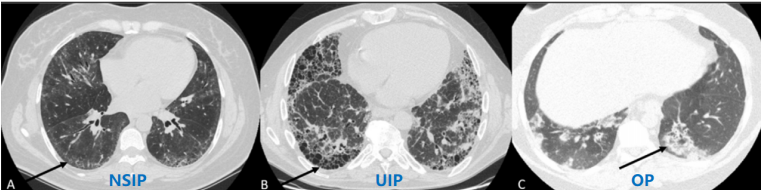

ASS肺部累及以非特异性间质性肺炎(NSIP)、机化性肺炎(OP)最为常见,可占所有ASS患者的78%~100%,部分患者可出现普通型间质性肺炎(UIP)及弥漫性肺损伤(DAD)表现。

图片

图源:Best Pract Res Clin Rheumatol, 2020, 34(4):101503.